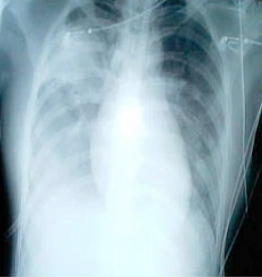

SARS患者患病三天的胸透照片

症状主要表现为:持续高烧(高于38℃),头痛和全身酸痛、乏力,干咳、少痰,部分病人有气促等呼吸困难症状,少数进展为呼吸窘迫综合征,肺部影像学显示肺炎改变。一般感冒病征包括发烧,咳嗽,头痛,可在数日后转好,并且一般没有肺炎迹象外周血白细胞计数无明显变化,淋巴细胞计数减少。抗菌药无效。SARS病毒能侵犯多种脏器,引起免疫系统对脏器的过度攻击,导致严重的脏器损伤。